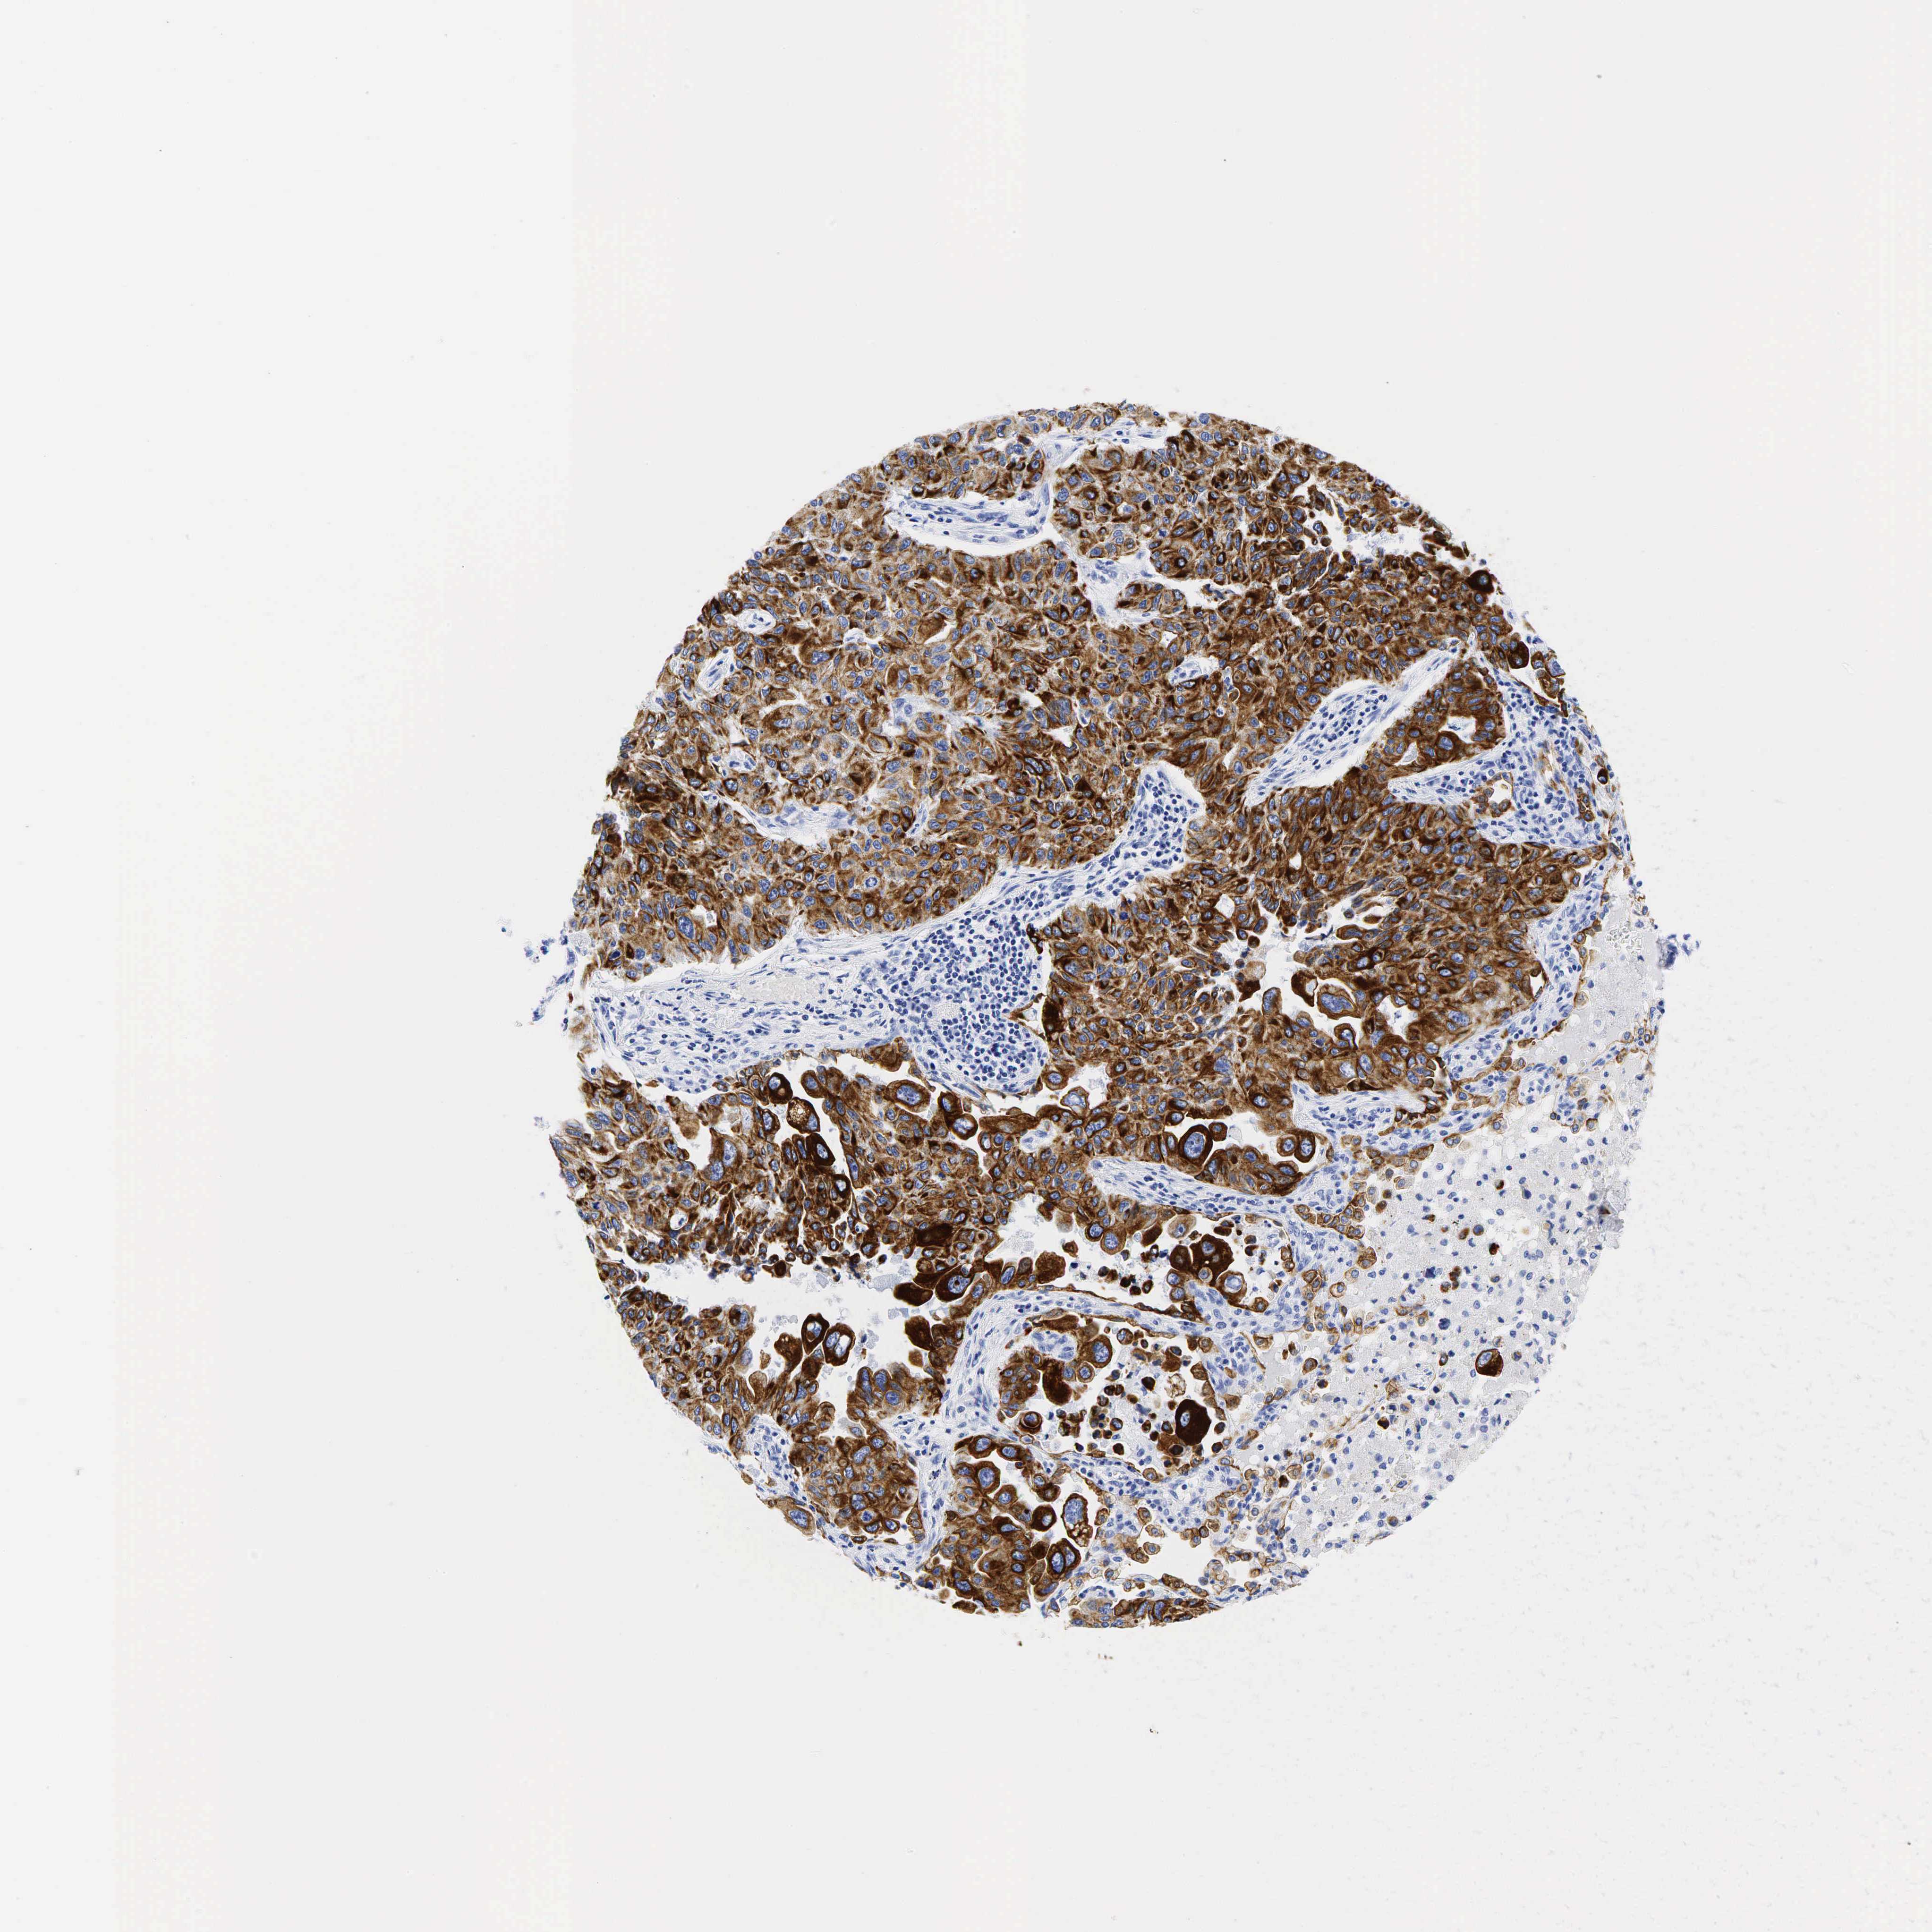

KRT19

CANCER LUNG CANCER Show tissue menu